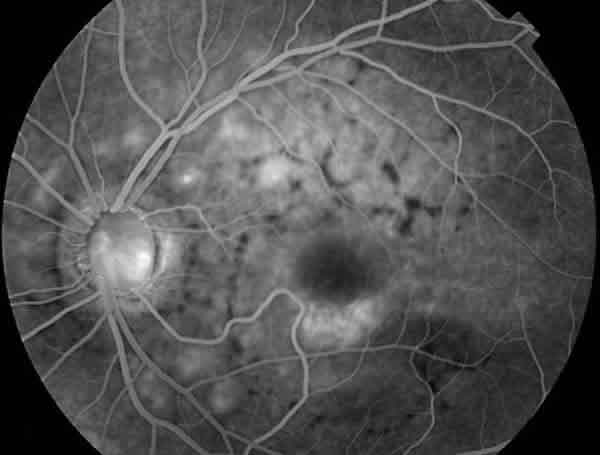

En la angiografía fluoresceínica (AFG) presentaba un patrón anular perimacular de aumento de la fluorescencia coroidea junto con un patrón reticular con efecto pantalla, siendo los flecos hipofluorescentes (figs. 4 y 5).

Fig. 4. AFG del OI del caso 1. Aumento de fluorescencia coroidea y patrón reticular con efecto pantalla.